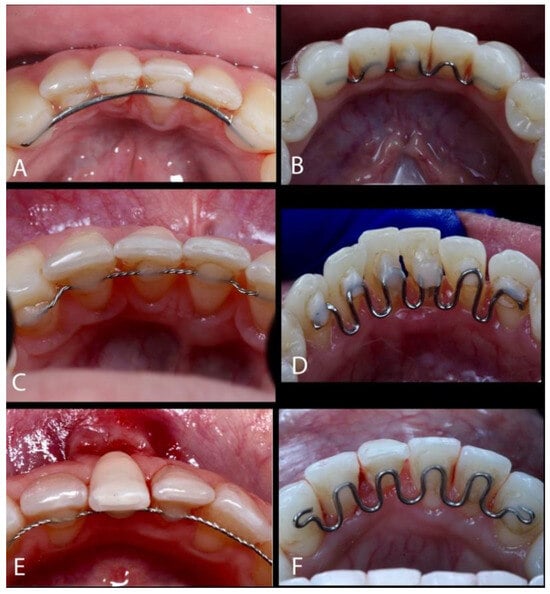

The Treatment of Gingival Recessions in the Lower Anterior Region Associated with the Use/Absence of Lingual-Fixed Orthodontics Retainers: Three Case Reports Using the Laterally Closed Tunnel Technique and Parallel Incision Methods

- Charavet, C.; Vives, F.; Aroca, S.; Dridi, S.M. “Wire Syndrome” Following Bonded Orthodontic Retainers: A Systematic Review of the Literature. Healthcare 2022, 10, 379. [Google Scholar] [CrossRef]